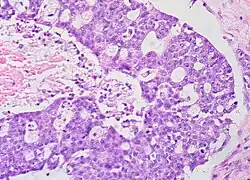

Micrograph of a mucinous ovarian carcinoma stained by H&E

Mucinous tumors include mucinous adenocarcinoma and mucinous cystadenocarcinoma.[29]

Mucinous adenocarcinoma

Mucinous adenocarcinomas make up 5–10% of epithelial ovarian cancers. Histologically, they are similar to intestinal or cervical adenocarcinomas and are often actually metastases of appendiceal or colon cancers. Advanced mucinous adenocarcinomas have a poor prognosis, generally worse than serous tumors, and are often resistant to platinum chemotherapy, though they are rare.[29]